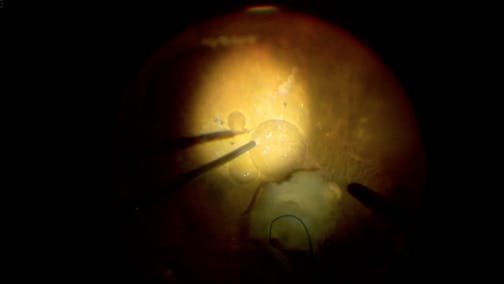

Optic Nerve Pit

Kourous A. Rezaei, MD